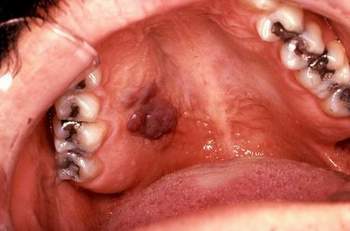

| Hình ảnh ung thư vòm họng. |